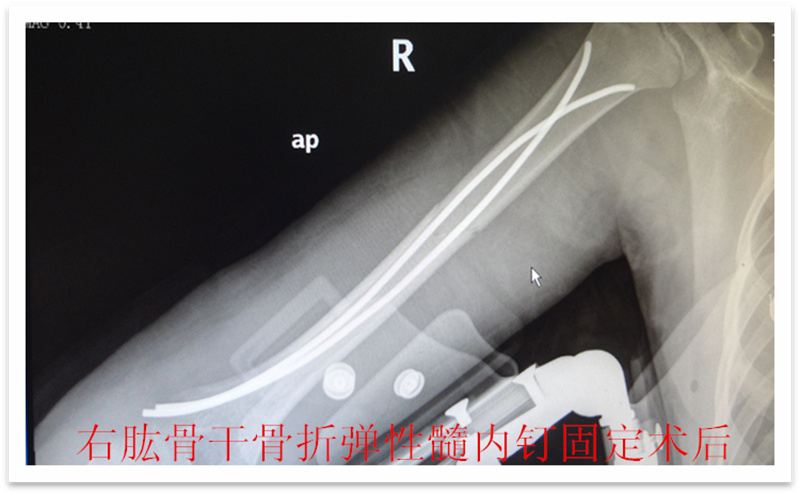

徐州市儿童医院科普:儿童骨折的微创治疗--四肢骨折的弹性髓内钉技术